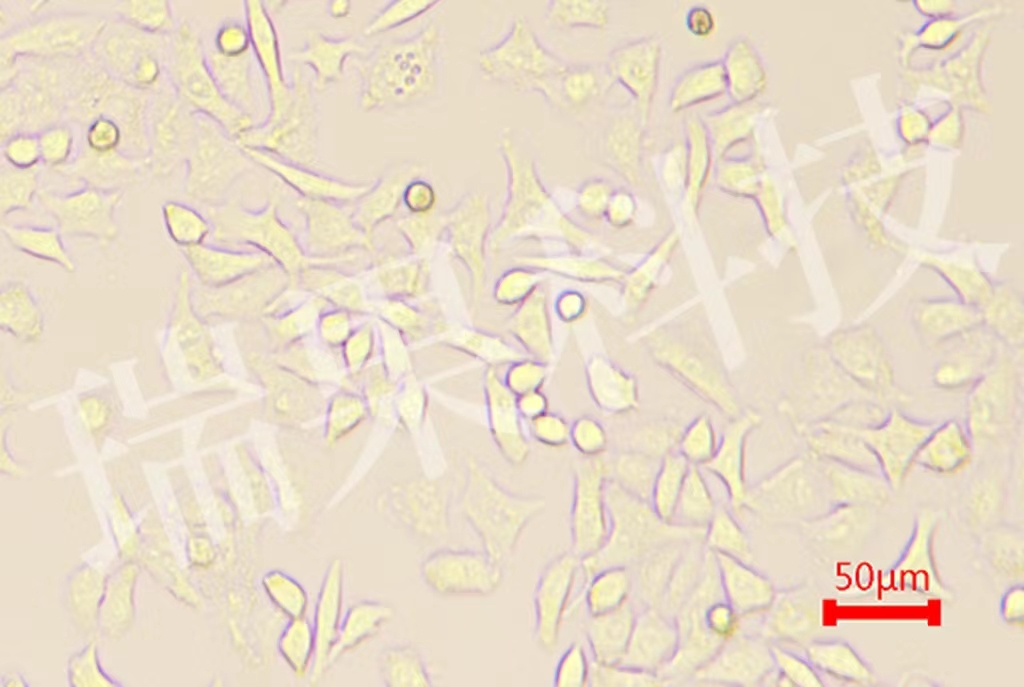

提供全面、專業的腫瘤動物模型構建與研究服務,覆蓋從基礎研究...